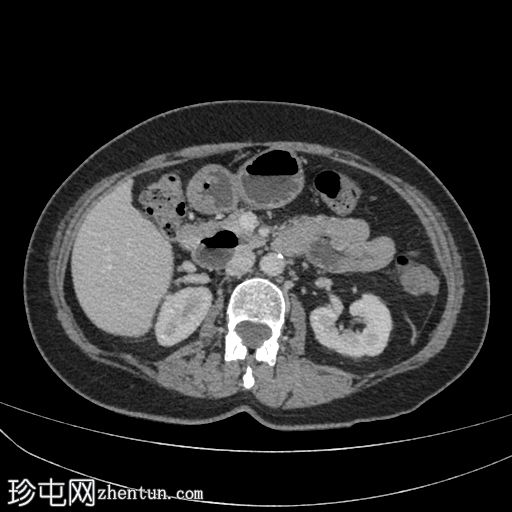

腹部CT显示十二指肠第二段和第三段可见气液平面,无并发症。未见其他异常。

病例讨论

这是十二指肠憩室的典型

影像

学表现和位置;通常无症状。

需注意的并发症包括穿孔、胆管梗阻和胰腺炎。